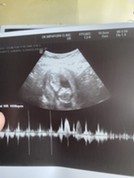

เรากำหนดคลอด 13 มิ.ย 64. ค่ะ แม่ๆน้ำหนักขึ้นมากี่โลแล้วค่ะ เราขึ้นเยอะมาก 5-6 โล 😭😭😭. อยากเห็นท้อง และภาพอัลตร้าซาวต์แม่ๆจังเลยค่ะ 10 week 3 day 🤰

กำหนดคลอด11มิถุนายนค่ะ ในใบอัลตร้าซาวด์มีที่บอกน้ำหนักน้องไหมคะ